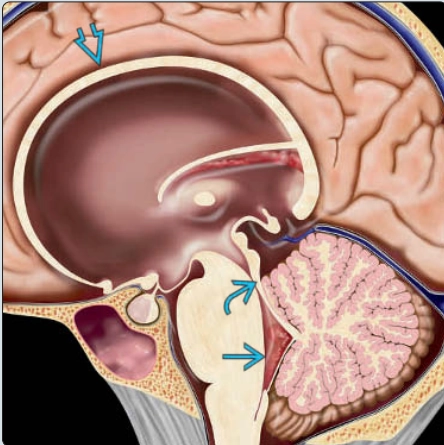

Dị dạng Dandy-Walker ở thai (Classic Dandy-Walker malformation)